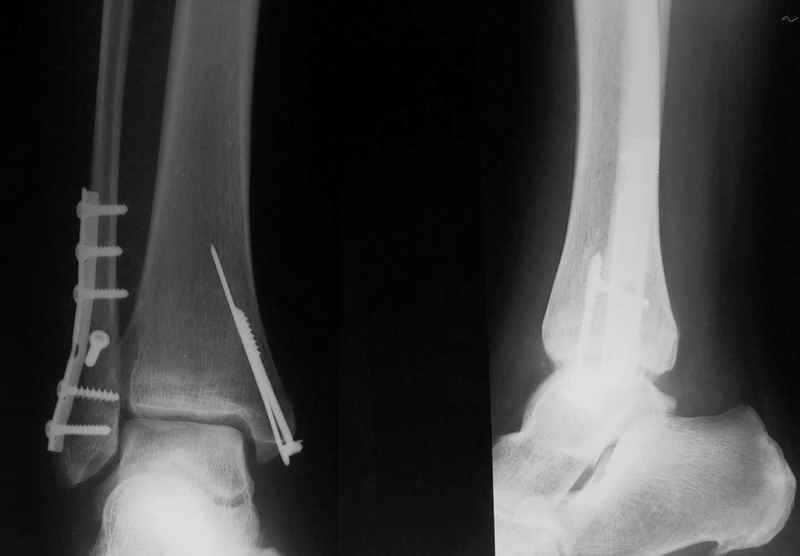

Стабильность г\ст сустава обеспечивается во-первых наружной лодыжкой (ключ), во-вторых задним краем б\б кости, в-третьих связками синдесмоза и межкостной мемраной, только в-четвертых медиальной лодыжкой (дельтовидной связкой. Это классика! А пяточной кости и плюсневых костей здесь нет! зачем их фиксировать? см. вложенный файл.

Коллега!Sorry,по-моему стоит провести винт через синдесмоз,а?Вроде бы контуры г\ст не совпадают,нет?Я дал бы компрессию на синдесмоз в положении полного разгиба стопы

>>Д.Б. - Коллега!Sorry,по-моему стоит провести винт через синдесмоз,а?Вроде бы контуры г\ст не совпадают,нет?Я дал бы компрессию на синдесмоз в положении полного разгиба стопы..

1. Винт никогда не стоит проводить "через" синдесмоз. Если и проводить, то выше синдесмоза.

2. Межберцовый винт должен быть только позиционным и должен удерживать синбесмоз, а не компремировать его

3 Контуры девственны: талокруральный угол, суперпозиция, медиальное пространство. Что не совпадает?

Вообще, этот больной через 2 месяца после травмы в футбол играл.